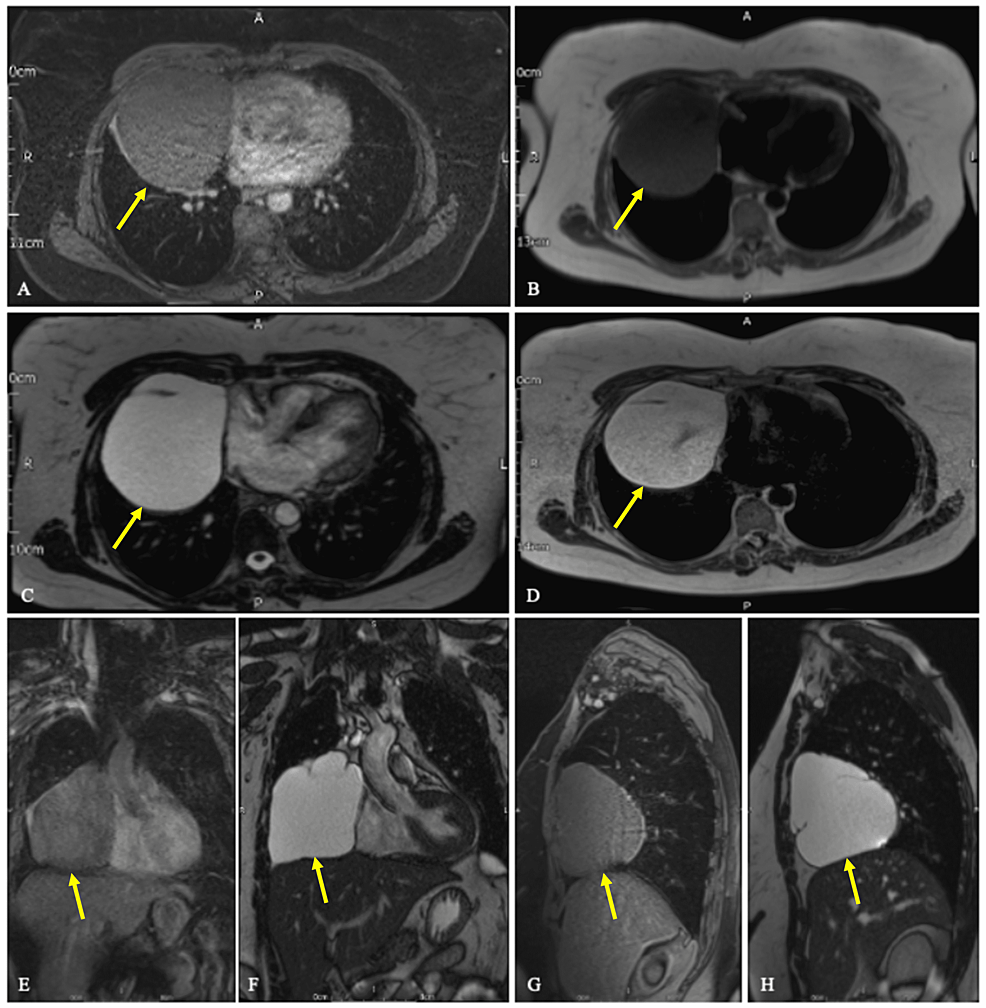

From www.cureus.com

Cureus An Incidental Finding of a Large Pericardial Cyst Water Density Lesion From a practical point of view, the approach to characterizing a focal liver lesion seen on ct begins with the determination of its. Slowly progressive peripheral nodular enhancement of arterial density. A cyst has a thin wall and may have thin septa. It may be an endothelial cyst or a. Liver lesions, also known as liver tumors or masses, are. Water Density Lesion.